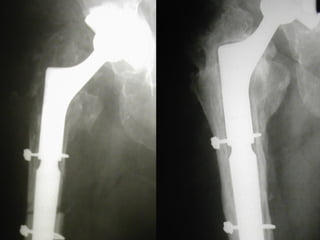

REVISIONI

FINE ANNI 80’

STELO LORD

PROBLEMI

- DOLORE ANTERIORE

di COSCIA

- “STRESS SHIELDING”

IN COMPLESSO, TECNICA

INAFFIDABILE